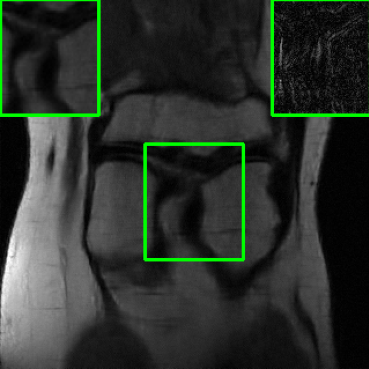

| Ground Truth | Vanilla MoDL | RS-E2E | SMUG |

![]() |

| PSNR = dB | PSNR = 23.41 dB | PSNR = 24.58 dB | PSNR = 28.91 dB |

| AT | Score-MRI | Deep-Equilibrium | Weighted-SMUG |

| PSNR = 28.67 dB | PSNR = 27.89 dB | PSNR = 24.13 dB | PSNR = 29.41 dB |

Results for the FastMRI Brain Dataset: we present the robustness results of the proposed approaches w.r.t. additive noise. In particular, the evaluation is conducted on the clean, noisy (with added Gaussian noise), and worst-case perturbed (using PGD for each method) measurements. Fig. 3 presents testing set PSNR and SSIM values as box plots for different smoothing architectures, along with vanilla MoDL and the other baselines using the brain dataset. The clean accuracies of Weighted SMUG and SMUG are similar to vanilla MoDL indicating a good clean accuracy vs. robustness trade-off. As indicated by the PSNR and SSIM values, we observe that weighted SMUG, on average, outperforms all other baselines in robust accuracy (the second and third set of box plots of the two rows in Fig. 3). This observation is consistent with the visualization of reconstructed images for the brain dataset in Fig. 4. We note that weighted SMUG requires longer time for training, which represents a trade-off. When comparing to AT, we observe that AT is comparable to SMUG in the case of robust (or worst-case noise) accuracy. However, the drop in clean accuracy (without perturbations) for AT is significantly larger than for SMUG. Furthermore, AT takes a much longer training time as it requires to solve an optimization problem (PGD) for every training data sample at every iteration to obtain the worst-case perturbations. Furthermore, we observe that its effectiveness is degraded for other perturbations including random noise as well as modified sampling rates shown in the next subsection. Importantly, the proposed SMUG and Weighted SMUG are not trained to be robust to any specific perturbations or instabilities, but are nevertheless effective for several scenarios.

Results for the FastMRI Knee Dataset: In Fig 5 and Fig 7, we report PSNR and SSIM results of different methods at two sampling acceleration factors for the knee dataset. Therein, we observe quite similar outcomes to those reported in Fig 3. Figs. 6 and 8 show reconstructed images by different methods for knee scans at 4x and 8x undersampling, respectively. We observe that SMUG and Weighted SMUG show fewer artifacts, sharper features, and fewer errors when compared to Vanilla MoDL and other baselines in the presence of the worst-case perturbations.